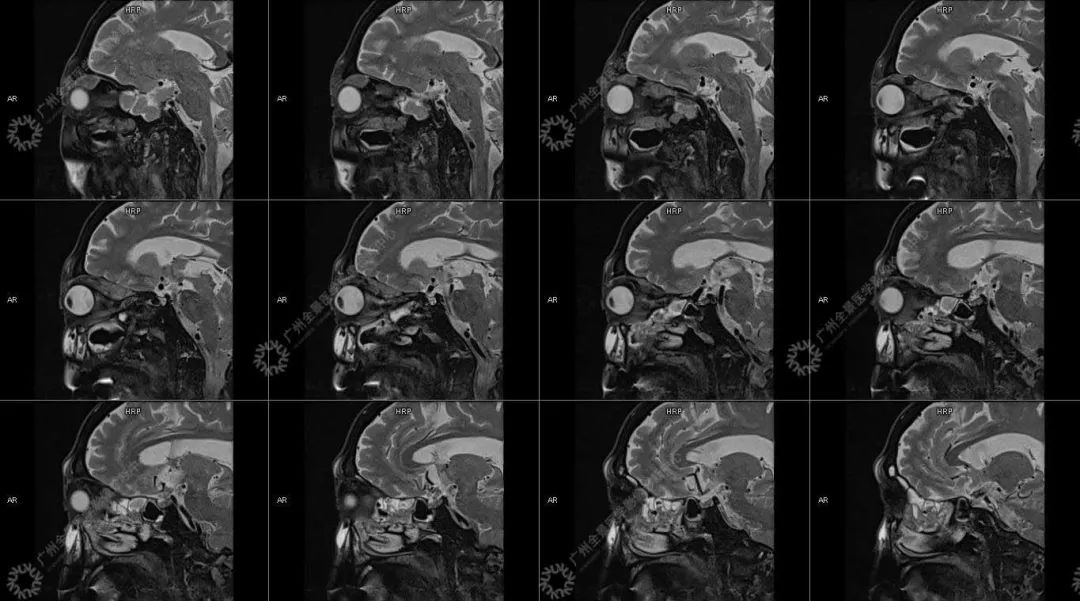

患者:男性, 71 岁

主诉:视力下降 2 年

现病史:双眼部隐痛、流泪,视力下降 2 年

结合影像及实验室检查,临床最终考虑 IgG4 相关性疾病。